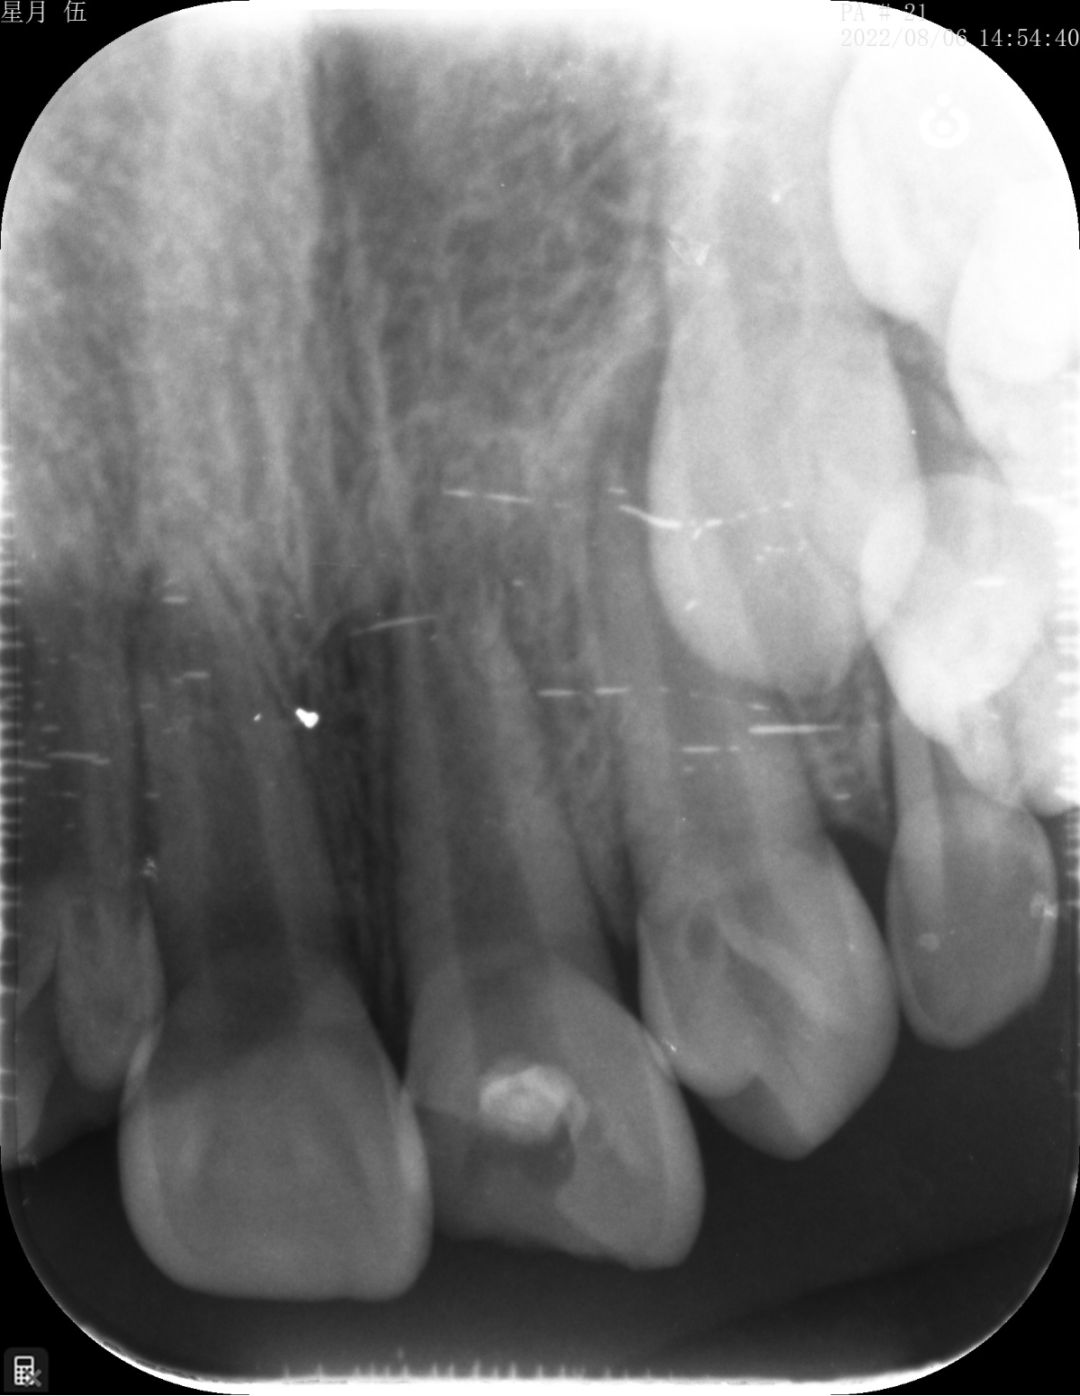

“起死回生”技术

“牙髓再生”技术是我科室率先在资阳市开展的生物组织学工程技术,利用自体血液促进仿牙髓组织再次发育,促进年轻恒牙牙根继续发育直至发育完成。相比传统技术,可以有效增加牙根的长度,粗度。

根尖炎症导致牙根停止发育

经过牙髓再生技术后,6个月后,根尖炎症消失,牙根长度增加,牙根的厚度增加